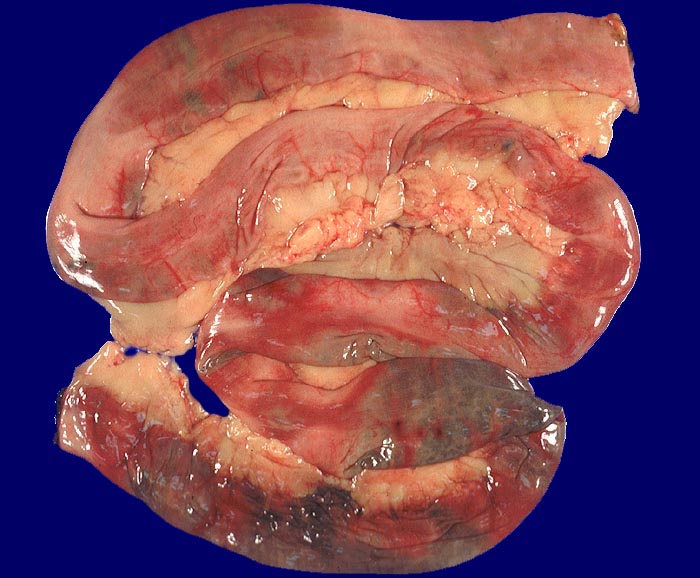

PathoPic ID 430 - embolischer Mesenterialinfarkt

embolischer Mesenterialinfarkt

vaskulär / Durchblutungsstörung

Dünndarm

Kardiovaskuläres System

Dunkle Verfärbung der Darmschlingen und injizierte Serosa.

Alter Myokardinfarkt Parietalthrombus. Frische Emboli in eröffneten Ästen der Arteria mesenterica superior.

Makroskopie